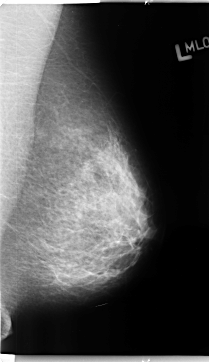

B_3142_1.LEFT_MLO

LEFT_MLO LINES 4704 PIXELS_PER_LINE 2712 BITS_PER_PIXEL 12 RESOLUTION 50 NON_OVERLAY